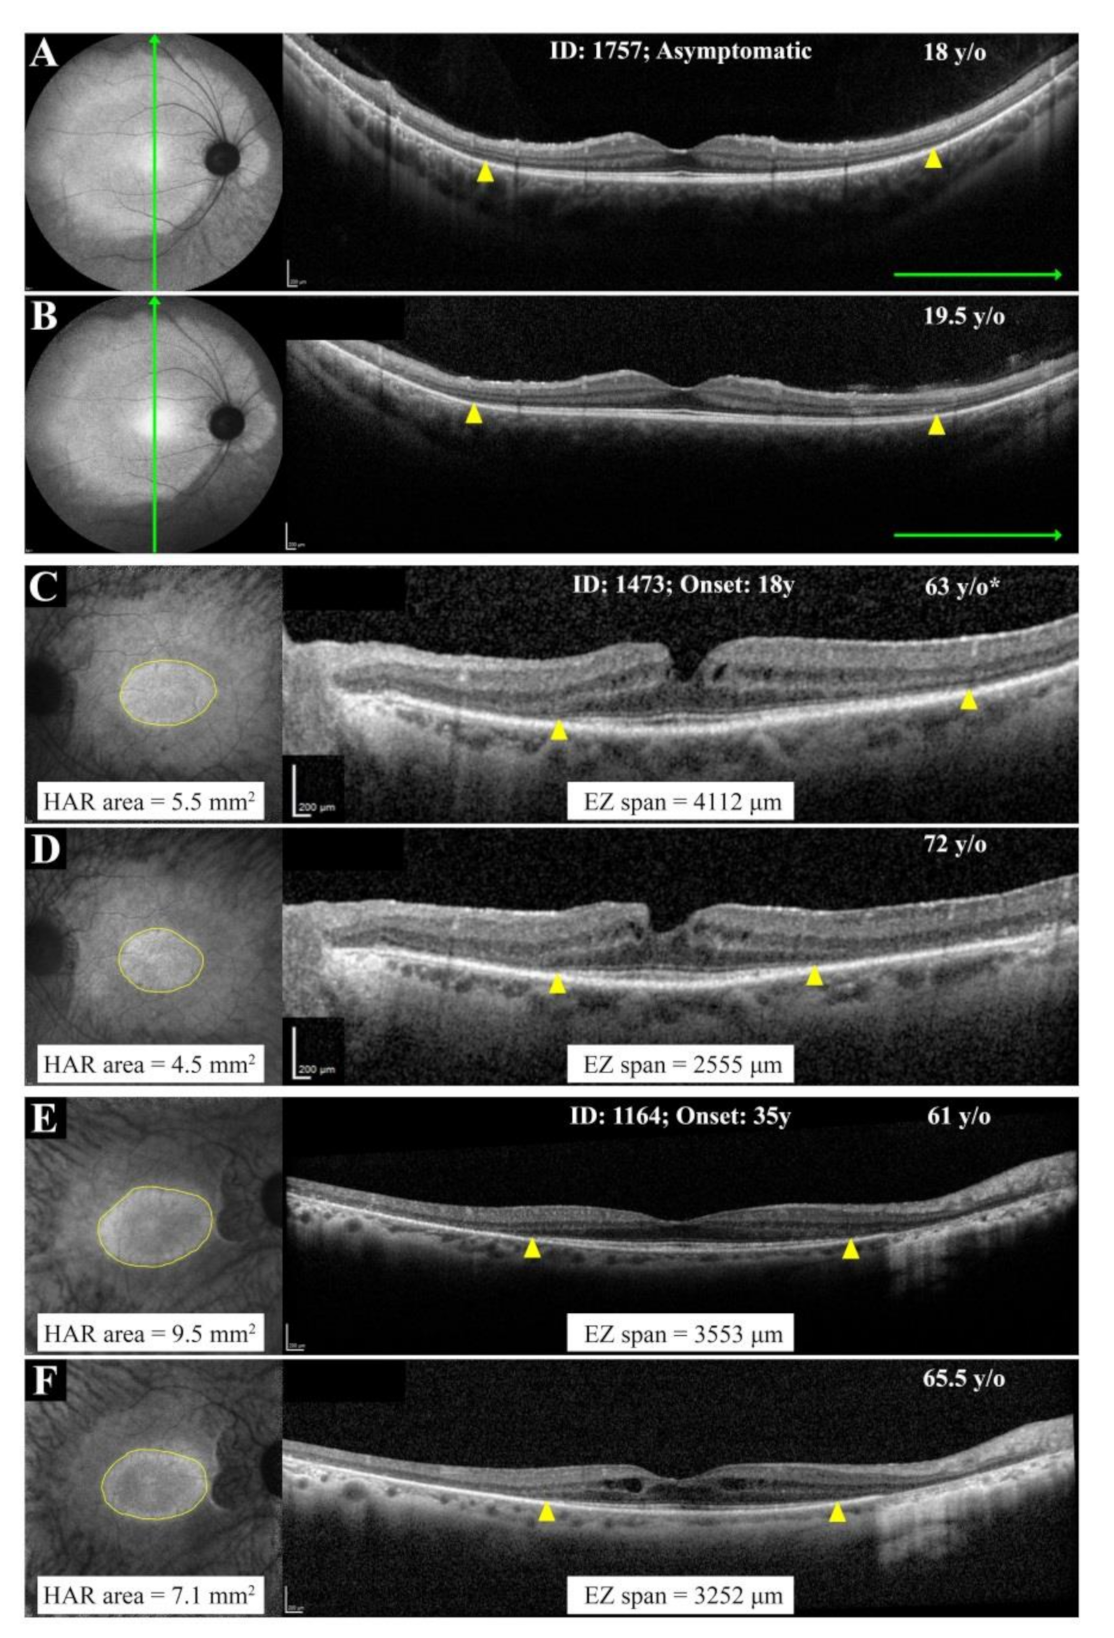

3.3. Natural History of Disease Progression

3.4. Phenotype Patterns

4.1. RP11 Phenotype Varies in Patients with Identical or Similar Mutations

4.2. RP11 Progression May Not Follow a First-Order Exponential Curve

4.3. Implication of Wild-Type vs. Mutant Allele in RP11 Phenotype